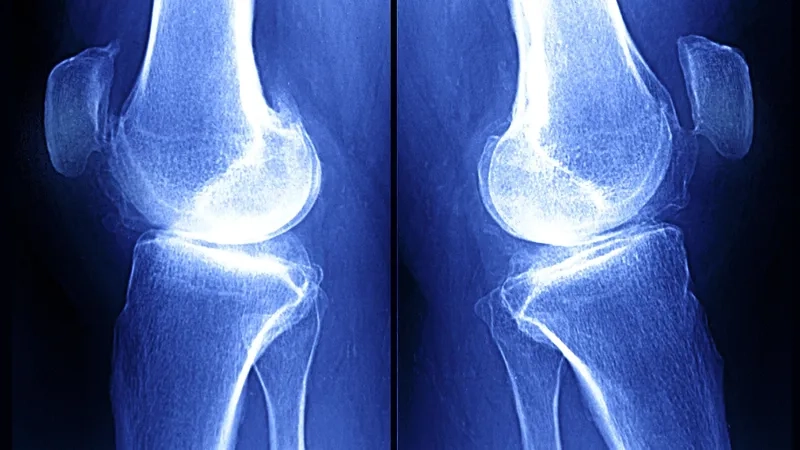

An X-ray showing arthritis in the knee